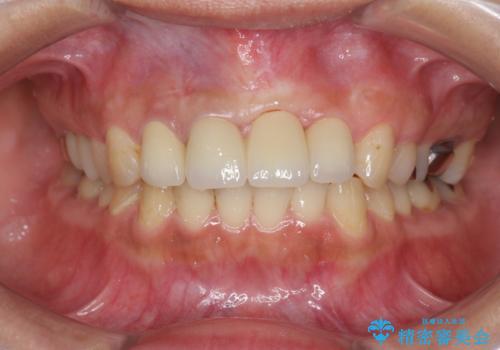

- 前歯の見栄えの悪さの改善を求めて来院されました。

左側の前歯には他院で埋入されたポジションの悪いインプラント補綴により歯冠長の長いクラウンが装着されており、感染による排膿も認められこのまま審美性を改善するのは難しい状態です。

不良インプラントを除去し最終的にブリッジによる補綴で審美性の改善を行うこと、その準備として骨の造成・歯肉の移植による歯の欠損部顎堤のボリュームを維持・増大を計画します。